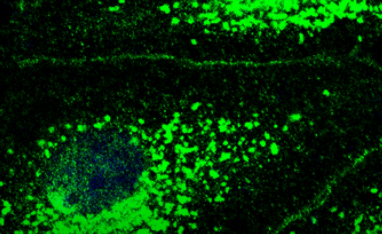

为了找出CFTR在肺血管中的作用以及当氯离子通道丢失时在分子水平上发生了什么,研究人员用一种抑制剂阻断了该通道并控制了细胞中氯离子的数量。然后他们使用了一种称为免疫荧光成像的特殊成像技术。

“我们看到抑制CFTR引发了分子级联反应,最终导致肺部血管开始渗漏,”主要作者、生理学研究所Kuebler团队的博士后LastiErfinanda博士说。“因此,CFTR实际上确实在肺水肿的发展中发挥了非常关键的作用。”